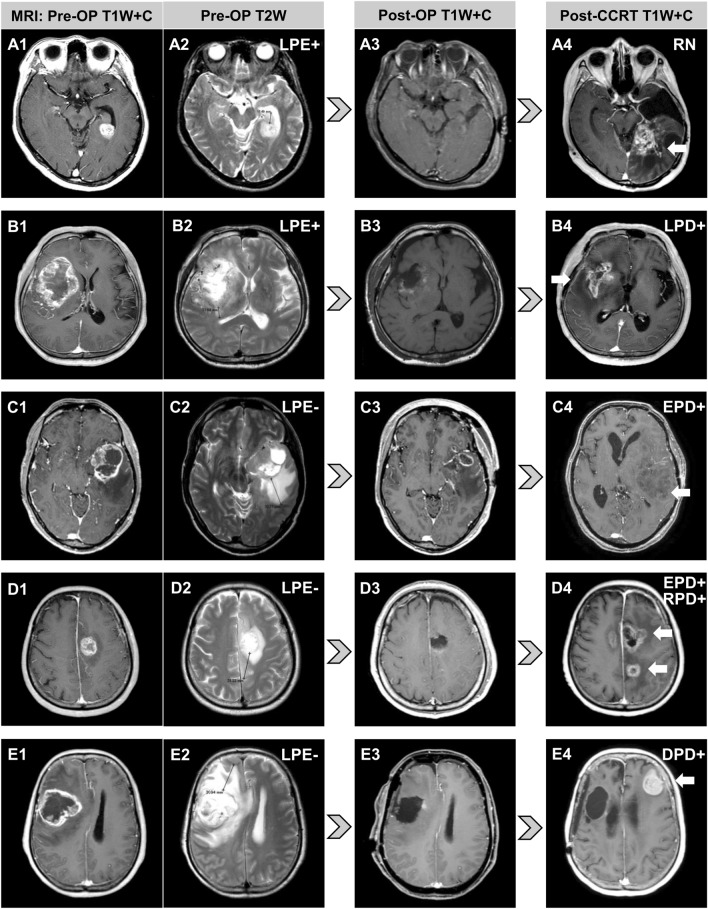

Diverse progression patterns evaluated by magnetic resonance imaging (MRI) after tumor resection and HDPB for five cases of glioblastoma with different PE extents are shown in Fig. 3. PE maximum extent and tumor maximum diameter were measured in axial, sagittal or coronal sections. The axial section is shown to facilitate illustration and interpretation. The arrows mark tumor progression. Patient A was LPE + before surgery (Fig. 3A) receiving GTR (Fig. 3A) and had radiation necrosis without tumor progression after HDPB (Fig. 3 A). Patient B was LPE + before surgery (Fig. 3B) receiving GTR (Fig. 3B) and had tumor progression confined to the tumor bed after HDPB (Fig. 3B). Patient C was LPE– before surgery (Fig. 3C) receiving partial resection (Fig. 3C) and had EPD after HDPB (Fig. 3C). Patient D was LPE– before surgery (Fig. 3D) receiving GTR (Fig. 3D) and had EPD to the contralateral hemisphere and regional PD corresponding to the preoperative PE area after HDPB (Fig. 3D). Patient E was LPE– before surgery (Fig. 3E) receiving GTR (Fig. 3E) and had distant tumor progression at the contralateral frontal lobe without local recurrence after HDPB (Fig. 3E). Eleven patients underwent salvage tumor resection due to tumor recurrence. The median survival after salvage surgery (Supplementary Table 3) for patients without and with distant PD was 20.6 and 8.4 months (p = 0.005), respectively.

Fig. 3.

Diverse progression patterns observed after tumor resection and high-dose proton boost for five glioblastoma patients according to their peritumoral edema statuses. The arrows mark tumor progression. A LPE + patient with radiation necrosis only. B LPE + patient with tumor progression confined to the tumor bed. C LPE − patient with EPD. D LPE − patient with EPD, extending into the contralateral hemisphere and regional PD. E LPE − patient with distant tumor progression at the contralateral frontal lobe. DPD distant progressive disease, EPD extended progressive disease, LPE limited peritumoral edema, OP operative, RN radiation necrosis, RPD regional progressive disease, T1W + C contrast-enhanced T1-weighted magnetic resonance imaging